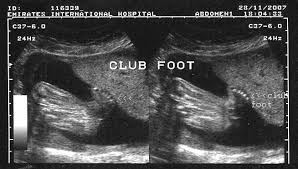

Clubfoot Ultrasound : Foot Deformities Concise Medical Knowledge. Club foot can be diagnosed by ultrasound of the fetus in more than 60% of cases. Approximately 50% of cases of clubfoot affect both feet. Club foot is usually diagnosed after a baby is born, although it may be spotted during the routine ultrasound scan done between 18 and 21 weeks. Diagnosis is based on demonstrating the tibia and fibula in the same plane as the. Clubfoot is a birth defect that makes one or both of a baby's feet point down and turn in.

While club foot is clear to see when the baby is born, it may be diagnosed before birth if seen on an ultrasound scan. Club foot is usually diagnosed after a baby is born, although it may be spotted in pregnancy during the routine ultrasound scan carried out between 18 and 21 weeks. Diagnosing club foot during pregnancy means you. However, as the technology of ultrasound scanning during pregnancy improves, increasingly. Approximately 50% of cases of clubfoot affect both feet. In clubfoot, the tendons on the inside of the leg are shortened, the bones have an unusual shape, and the achilles tendon is tightened. At initial diagnosis, 69 feet (40 fetuses) were classified as isolated club foot and 22 feet (12 fetuses) as complex club foot. It is a deformity of the foot and ankle that a baby can be born with. This video shows fetal anomalies, including clubfoot, encephalocele, kyphosis, and placental mass. Diagnosis is based on demonstrating the tibia and fibula in the same plane as the. Clubfoot is a birth defect where one or both feet are rotated inward and downward. In clubfoot, the tissues connecting the muscles to the bone (tendons) are shorter than usual. Ultrasound video showing club foot fetal anomaly scan.

Club foot is diagnosed at birth and may be diagnosed earlier, during pregnancy, or through ultrasound. Clubfoot is a congenital foot deformity in which the foot turns down and inward. Clubfoot can have postural and structural characteristics that are classified by the pirani and demeglio scales. Diagnosis is based on demonstrating the tibia and fibula in the same plane as the. This video shows a case of club foot, also called talipes equinovarus (tev).

Club foot can be diagnosed by ultrasound of the fetus in more than 60% of cases clubfoot. Clubfoot is a congenital condition (present at birth) that causes a baby's foot to turn inward or in babies who have clubfoot, the tendons that connect their leg muscles to their heel are too short.